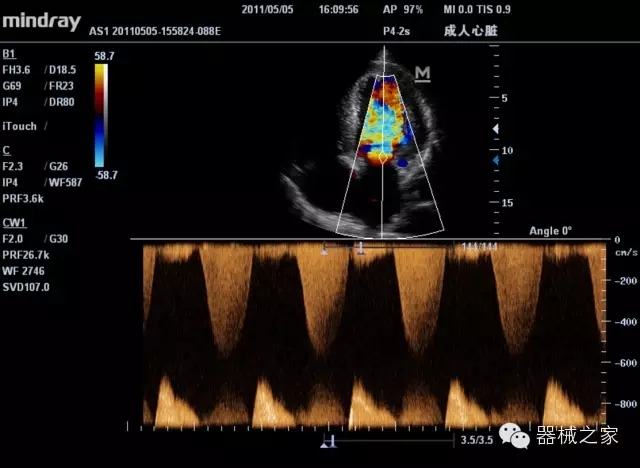

經(jīng)典產(chǎn)品:M7(星鉆)

臨床圖片賞析

產(chǎn)品特點(diǎn)

·裝載有采用Multi-Core多核處理的非嵌入式平臺(tái),成像效率大大提高,并且能夠給用戶帶來高速、多任務(wù)并行信號(hào)處理體驗(yàn);

·優(yōu)秀的圖像效果、強(qiáng)大的功能體驗(yàn)、豐富的探頭選擇、合理的便攜式設(shè)計(jì),全中文顯示及病人管理界面,使得M7在任何場合、任何時(shí)候都能快速響應(yīng)更好的心血管、腹部、婦產(chǎn)、小器官等常規(guī)超聲檢查以及肌骨、神經(jīng)、顱腦、術(shù)中等新興領(lǐng)域的使用需求;

8倍波束并行處理系統(tǒng)

·在便攜式緊湊平臺(tái)上采用更多倍波束并行接收信號(hào)處理模式,無論二維還是彩色血流圖像狀態(tài)下,擁有更靈敏的回波頻移捕獲能力,大大提高時(shí)間分辨率,尤其使得心血管表現(xiàn)更為突出;

PSHI?寬帶頻移諧波技術(shù)

·在普通組織諧波的基礎(chǔ)上,通過精確控制的波束形成器,發(fā)射兩組具有相位偏差反向的信號(hào),并采用并行信號(hào)處理,數(shù)字化合成并采樣回波信號(hào),在高靈敏度的濾波器的處理過程中獲取更純凈的諧波信號(hào),使圖像具有更加出眾的細(xì)節(jié)分辨率;

iClear®+iBeam?

·智能化按線復(fù)合多角度獲取聲束的原始信號(hào),配合智能化的斑點(diǎn)噪聲識(shí)別及控制處理技術(shù),整體提高組織結(jié)構(gòu)細(xì)節(jié)分辨率,任何時(shí)候都能快速響應(yīng),更好的滿足心血管的使用需求;

支持全新3T工藝探頭群

·包括探頭材料、結(jié)構(gòu)設(shè)計(jì)、加工工藝三方面的革新技術(shù)給圖像帶來品質(zhì)的飛躍;